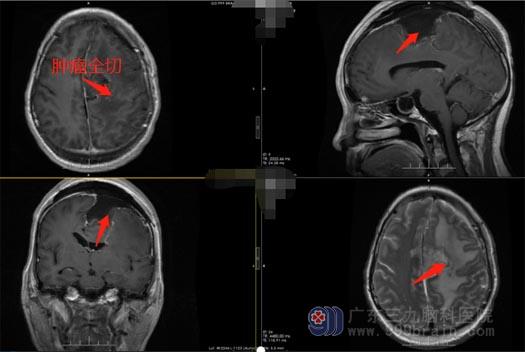

经过缜密的术前讨论,由王国良主任主刀,带领神经外五科治疗团队为黄阿姨在全麻下施行左侧额顶部镰窦旁脑膜瘤切除术。术后,黄阿姨恢复顺利,手脚活动比术前大大好转,也没有头晕头痛,手术后第八天,黄阿姨顺利康复出院了。